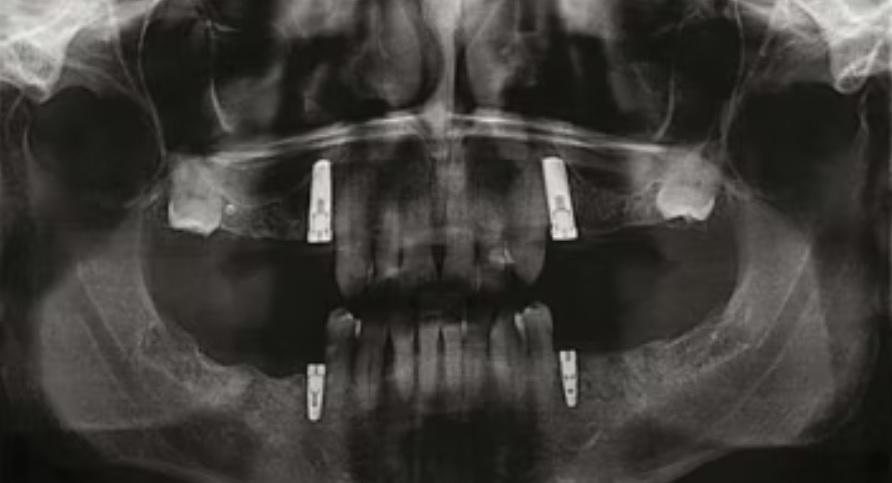

Панорамная рентгенограмма, сделанная перед удалением.

Примерно через 19 месяцев ортопантомограмма выявила кариозные поражения на нескольких зубах. Два коренных зуба на верхней челюсти не поддавались восстановлению, и их пришлось удалить. На еще одном зубе было проведено эндодонтическое лечение и установлена металлокерамическая коронка.